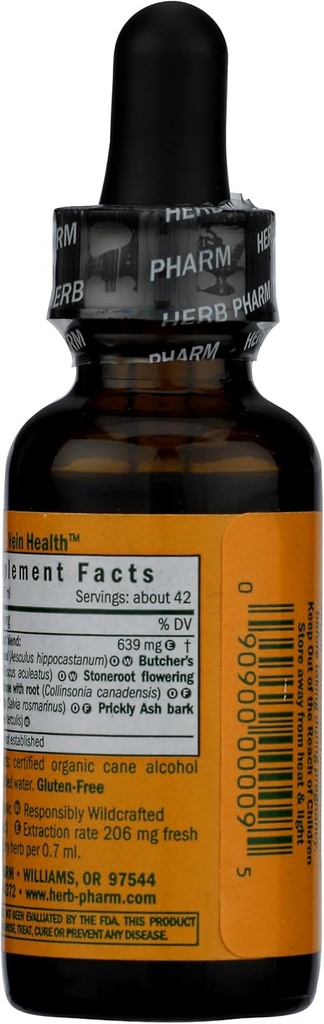

Suggested use: SHAKE WELL BEFORE USING Two to four times per day take 30 to 40 drops in a little water.

Proprietary Extract Blend: Amt Per Serving: % Daily Value :N/A,Horse Chestnut seed (Aesculus hippocast) Amt Per Serving: % Daily Value :N/A,Butcher's Broom rhizome (Ruscus acu.) Amt Per Serving: % Daily Value :N/A,Stoneroot lf., flr., & rhizome (Collinsonia can.) Amt Per Serving: % Daily Value :N/A,Rosemary leafy tips (Rosmarinus officinalis) Amt Per Serving: % Daily Value :N/A,Prickly Ash bark (Zanthoxylum c.h.) Amt Per Serving: % Daily Value :N/A,,Other Ingredients: Certified organic alcohol (58-66%) and distilled water.

| Ingredients | Proprietary Extract Blend: Amt Per Serving: % Daily Value :n/a, Horse Chestnut Seed (aesculus Hippocast) Amt Per Serving: % Daily Value :n/a, Butcher's Broom Rhizome (ruscus Acu.) Amt Per Serving: % Daily Value :n/a, Stoneroot Lf., Flr., & Rhizome (collinsonia Can.) Amt Per Serving: % Daily Value :n/a, Rosemary Leafy Tips (rosmarinus Officinalis) Amt Per Serving: % Daily Value :n/a, Prickly Ash Bark (zanthoxylum C.h.) Amt Per Serving: % Daily Value :n/a, Other Ingredients: Certified Organic Alcohol (58-66%) And Distilled Water. |